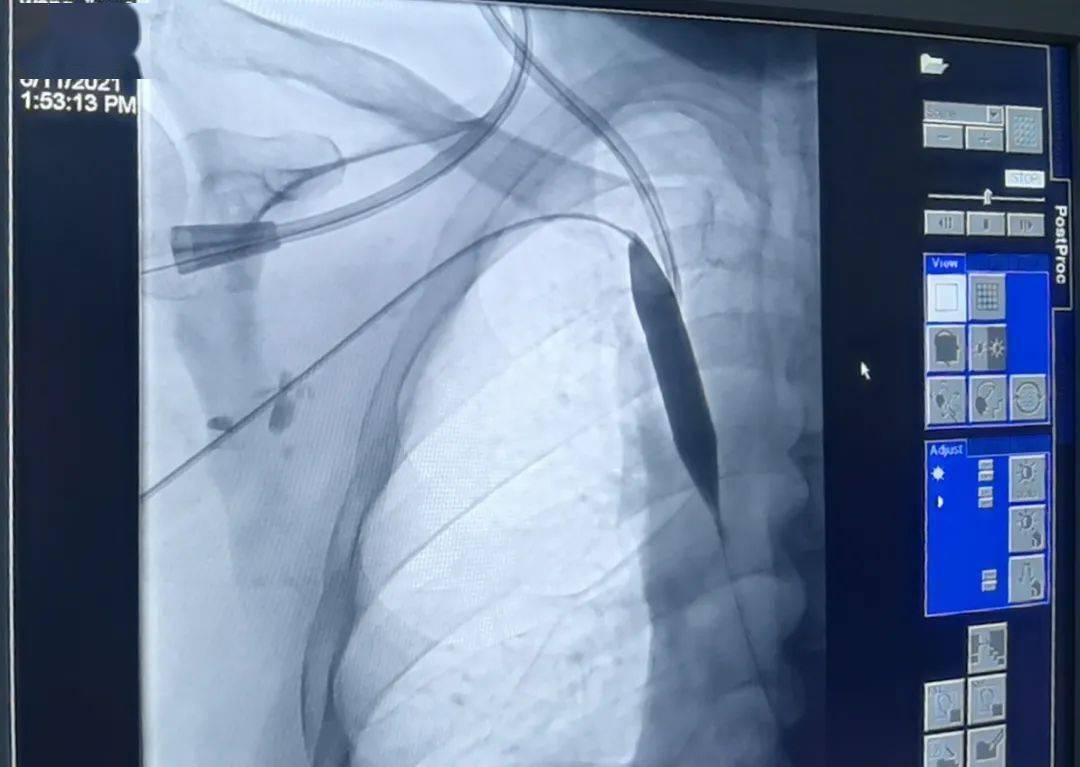

【医疗案例】内分泌肾内科成功独立开展首例数字减影血管造影术下中心

蚌埠市第二人民医院新dsa机房启用 脑血管造影一例

脑血管造影

血管造影

脑血管造影术